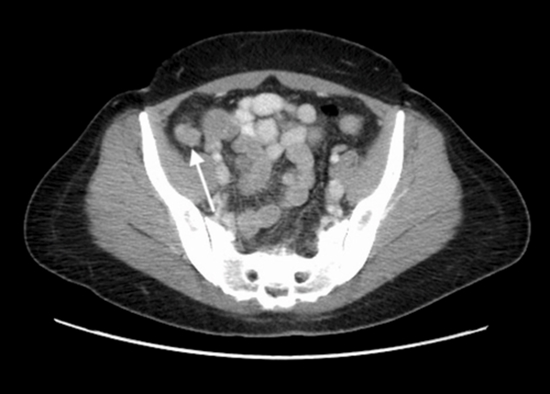

Imaging is crucial in evaluating women with suspected appendiceal endometriosis (AE), as the condition often mimics acute or chronic appendicitis and presents a diagnostic challenge. While modalities like ultrasound (US), computed tomography (CT), and magnetic resonance imaging (MRI) can help identify abnormalities, their findings are frequently nonspecific. Therefore, awareness of imaging features is essential for accurate diagnosis and management, though definitive confirmation still relies on histopathological examination after surgical excision. Objectives:

Twenty-six out of the total number of patients who underwent CT (30) had positive findings (86.6%), while 7 out of the total number of patients who underwent MRI (11) and 11 out of the total number of patients who underwent sonography (13) also had positive findings (63.6% and 84.6%, respectively). The mean age of the patients was 37.2 ± 7.07 years. Out of the total sample, 8 patients were pregnant. The overall imaging findings were: Normal (6 cases, 15%), wall thickening (9 cases, 22.5%), mass (15 cases, 37.5%), cystic mass (1 case, 2.5%), solid lesion in the left ovary (1 case, 2.5%), mucocele (3 cases, 7.5%), intussusception (4 cases, 10%), obstruction (5 cases, 12.5%), suspected obstruction (1 case, 2.5%), appendicitis (4 cases, 10%), fluid (11 cases, 27.5%), and abscess (3 cases, 7.5%). Conclusion:

Right lower quadrant (RLQ) mass and bowel wall thickening are the most commonly reported findings in patients with AE. Further studies are required to retrospectively evaluate the imaging findings of the appendix in pathologically confirmed AE after pelvic surgery.